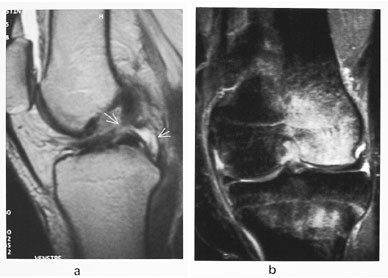

I opererte menisker kan det ved MR uten artrografiteknikk være vanskelig å avgjøre om det foreligger en reruptur. Hvis det er et høysignalområde som går mot reseksjonsranden, er det umulig å avgjøre om det er reruptur eller arrvev (6). Figur 5 viser skjematisk hvordan det kan se ut. MR-artrografi med direkte instillasjon av fortynnet gadolinium med påfølgende manipulasjon av kneleddet vil gjøre diagnostiseringen lettere. Dersom høysignalet blir like høyt som kontrastvæsken, må det være en kommunikasjon forenlig med ruptur. Dersom signalet er lavere enn kontrastvæsken, foreligger det kun arrvev (fig 6).

Korsbåndene er intraartikulære, men ekstrasynoviale strukturer og er viktige stabilisatorer av leddet. Det fremre (ACL), som kan variere i tykkelse, skades hyppigere enn det normalt bredere bakre (PCL). Tegn på ruptur er som for ligamenter beskrevet over (fig 7). Av og til kan det være vanskelig å avgjøre om det foreligger ruptur av fremre korsbånd. Indirekte tegn er beinkontusjon i laterale femurkondyl, spiss vinkel på bakre korsbånd og tegn på subluksasjon av tibiaplatået dorsalt.

Opererte korsbånd og korsbåndplastikker kan vurderes ved hjelp av MR (fig 8). Eventuelle skruer i henholdsvis laterale femur og mediale tibiakondyler vil ikke gi forstyrrende artefakter.